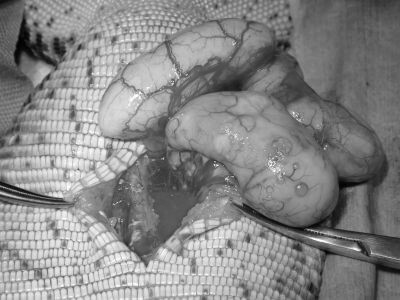

全身麻酔をかけてお腹を開けると、中から腹水と変形した卵、どろどろになった卵胞が見つかりました。

卵胞は破れてお腹の中に漏れ出しており、肺まで卵の素材がべったり付いていました。

左右の卵巣と卵管を全て取り出し、お腹をしっかり洗浄して手術終了となりました。